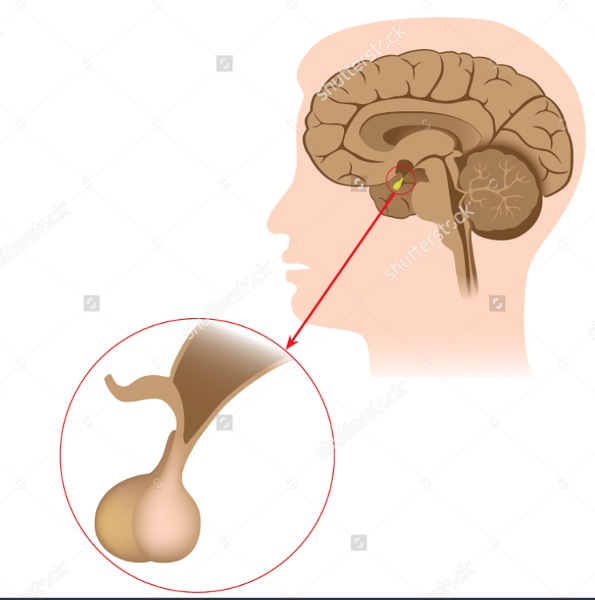

Pituitary Gland

Posterior Pituitary